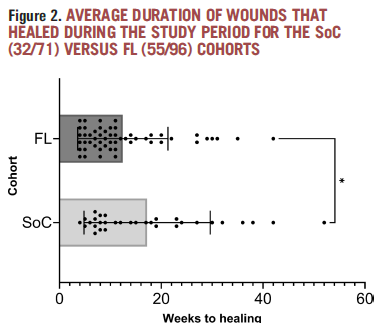

Bacterial fluorescence imaging as a predictor of skin graft integration in burn wounds

Hanson-Viana, E. et al. Burns 2024